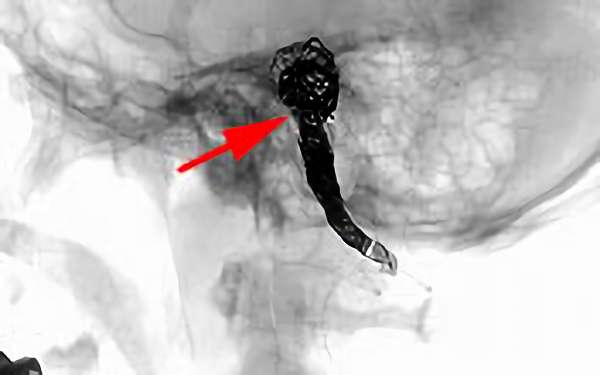

No.1631 手術前